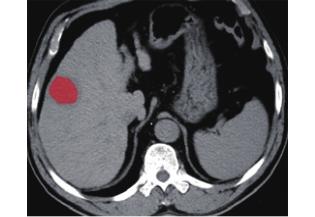

1.3.2 ROI 的定義 利用 Mazda 4.6[3,20]紋理分析軟件加載之前保存的 bmp 格式的圖像,在病灶區域手動畫出 ROI(圖 2、3)。為了最大程度地減少容積效應的影響,手動畫出 ROI 范圍在距病灶內側緣 2~3 mm。